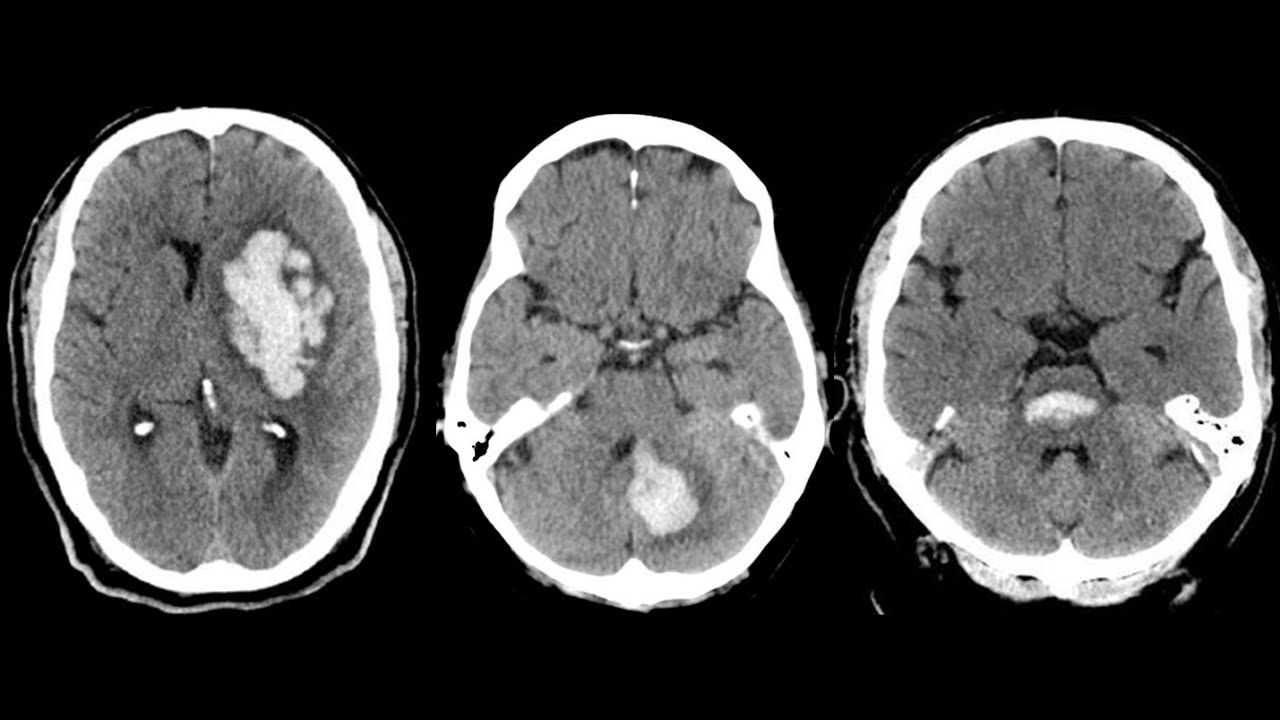

escuro substância branca branca substância cinzenta cinza T2 líquor Branco substância Branca escura substância cinzenta mais clara o contrário de T1 vamos falar um pouco sobre T1 com contraste o contraste usado na ressonância magnética é o gadolin e a gente faz o contraste sempre na sequência T1 você faz T1 antes do contraste Aí você faz todas as outras sequências T2 flare SW w de fusão e você injeta o contraste na veia e repete a sequência T1 Então você vai ter T1 sem contraste e T1 com contraste E aí você compara um com o outro o princípio

é que o contraste o gadolínio Brilha em T1 vai ficar branco em T1 então existem estruturas que realçam normalmente veja aqui é um T1 líquor escuro substância branca branca substância cinzenta cinza aqui é um T1 com contraste com gadolin veja que os vasos ficam com hipersinal ficam brancos Porque eles estão cheios de contraste veja aqui o seio sagital superior aqui e aqui estão branquinhos Porque estão Chei de contraste veja que eles estavam escuros aqui no T1 sem contraste outras estruturas que realçam de maneira fisiológica são plexo coroide eh Aqui não está representado mas a ase

da hipófise o infundíbulo da hipófise e a aden hipófise realçam normalmente Existem algumas outras estruturas que realçam por exemplo a duram Mat em alguns locais elas ela pode ter um Realce discreto menor que 2 MM de espessura e não contínuo e Por que que é importante o contraste porque quando você tem uma quebra da barreira emata encefálica seja por um processo inflamatório ou desmelenada [Música] vai ficar com hipersinal vai impregnar isso vai mostrar pra gente que ali tem quebra de barreira imato encefálica veja T1 sem contraste corte coronal a gente já via que tinha uma

alteração de sinal nessa região fez o contraste injetou o gadolínio veja como houve uma impregnação um Realce do córtex da substância Branca subcortical nessa região um reals Giri fore nessa região então a aqui aonde realçou há uma quebra da barreira hematoencefálica vamos falar um pouquinho sobre T1 com saturação de gordura voltando nesta imagem a gente vê que a gordura Brilha em T1 assim como Brilha em T2 Também Veja a gordura do tecido subcutâneo apresentando hipersinal em T1 Veja a gordura orbitária aqui intraconal e extraconal brilhando com hipersinal em T1 Veja a gordura aqui no tecido